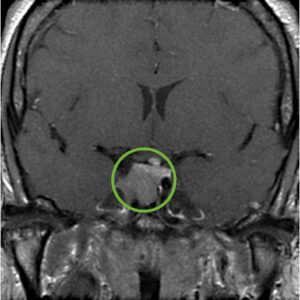

Following hormonal testing that confirms acromegaly, all the other pituitary hormones should be tested and an MRI of the pituitary with gadolinium contrast should be performed to confirm the presence of a pituitary adenoma. In the vast majority of individuals, an adenoma will be seen, typically a macroadenoma (larger than 1 cm in diameter).

First-line Treatment of Acromegaly – Endonasal Surgery

Fortunately, there are excellent treatments for acromegaly, starting with surgery, then medical therapies and lastly, focused radiation or radiosurgery. After diagnostic confirmation of acromegaly, endonasal transsphenoidal adenoma removal is considered first-line treatment. When performed by an experienced pituitary surgery team, long-term remission rates average 70- 80% and the risk of major surgical complications is very low, including a risk of new pituitary gland failure of less than 5%. The success rates are highest (typically greater than 85%) in patients with clearly defined non-invasive microadenomas (less than 1 cm in diameter) as seen on MRI. For patients with invasive adenomas, adenomas greater than 2 cm in diameter, or those with markedly elevated GH and IGF-1 levels, remission rates are substantially lower (typically ranging from 40-60%).